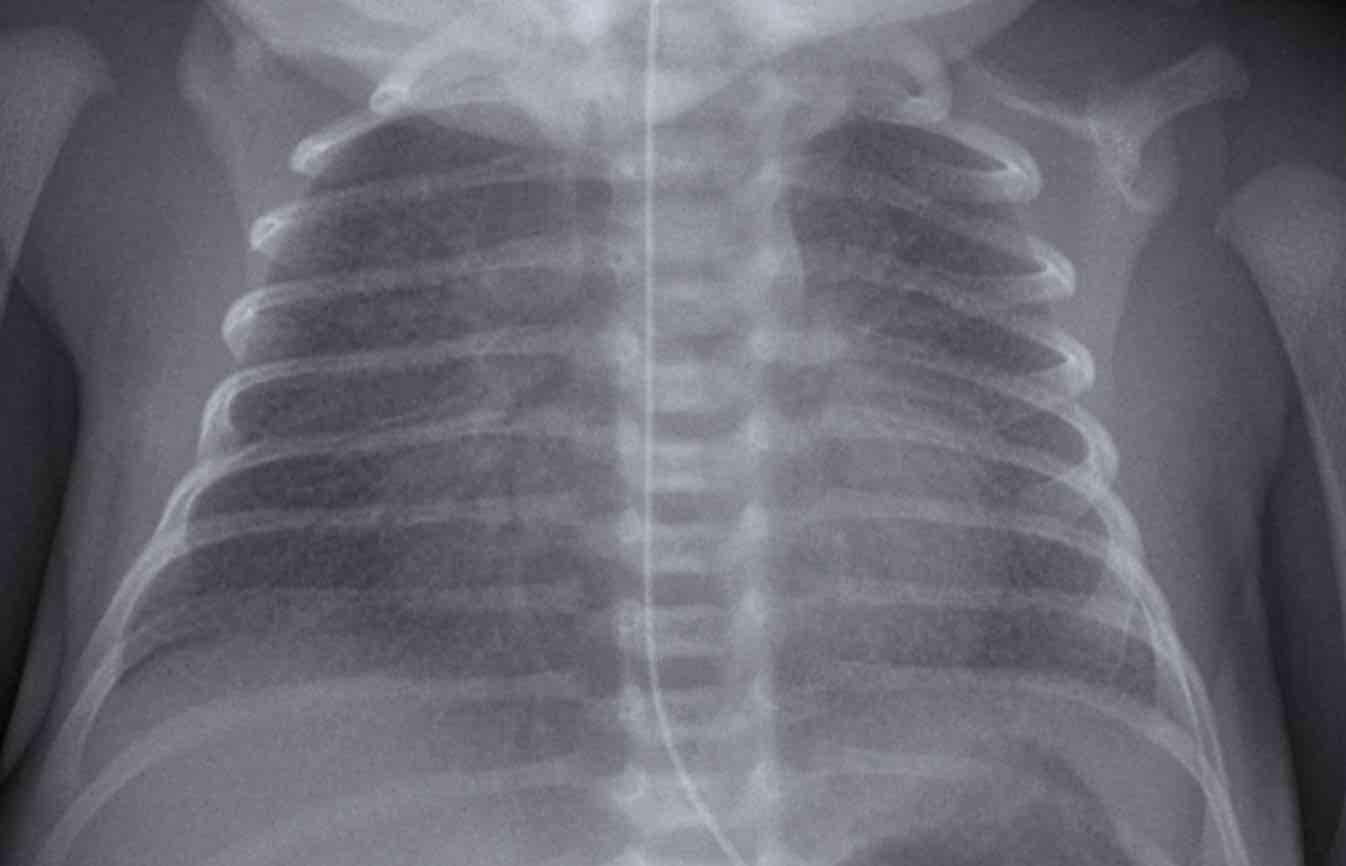

Hình ảnh

Trẻ sơ sinh một ngày tuổi, tuổi thai 27 tuần.

Mờ dạng hạt cả hai phổi.

Mạch máu và bóng tim được hiển thị rõ ràng.

Conclusion: RDS grade 1.